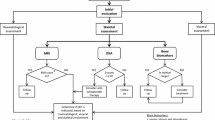

EFD describes a distinct abnormality of remodelling of the metaphyseal-diaphyseal areas with a progressive enlargement of the metaphyseal area, due to local bone marrow infiltration by Gaucher cells [31]. This leads to a lack of the typical concave di-metaphyseal curve resulting in an Erlenmeyer flask-like appearance. The sites affected are: the distal femora, occasionally also within the metaphyseal region of other tubular bones, and the proximal tibia or humerus. These changes occur before puberty, after which the bone alteration develops progressively. Modeling deformities, particularly the EFD in the distal femur, are often-described (30–45 % of adults) (Fig. 1), although they appear to be asymptomatic and not pathognomonic for GD. There is no relationship between this radiologic finding and other skeletal complications of GD [31].

Monitoring of bone disease in children and adults for initial assessment is carried out with X-ray examination of the femora, spine, and any other symptomatic sites. X-ray is commonly used for the detection of fractures, dislocation of joint replacements, the evaluation of joint arthroplasty, and can detect local deformities of bone including EFD, cystic or tumorous lesions, and localized cortical thinning [39]. However, X-ray shows a low sensitivity in detecting morphological bone manifestations in GD [39]. X-ray survey is useful at first assessment, and it is repeated only if there is a medical reason, while BMD or MRI can be used for follow up [22, 40].

MRI has high sensitivity for all kinds of skeletal pathologies in GD [39]. T1-weighted MRI is recommended to detect and quantify the extent of marrow infiltration, and T2-weighted MRI is recommended to identify focal lesions, active bone infarcts, osteonecrosis, and osteomyelitis. T1-weighted and T2-weighted spin echo sequences, short tau inversion recovery sequences, and turbo spin echo are different MRI modalities used in the evaluation of bone involvement in GD [39]. MRI spin echo sequences can show the fat content of bone marrow in adults [39]. Normal yellow marrow creates a hyperintense T1 and an intermediate to hyperintense T2-weighted signal; instead, the infiltration of bone marrow by Gaucher cells creates hypointense signals. ERT, determining the reduction of Gaucher cell deposition, increases fatty yellow marrow and therefore a normalization of signal intensity. MRI is the method of choice to evaluate the extent of bone disease prior to therapy and during follow-up in patients on therapy, and is also the most sensitive method to detect femoral head necrosis [39]. Quantitative chemical shift imaging (QCSI) is a quantitative MRI technique that measures fat content in the axial bone marrow and the extent of its displacement by Gaucher cells. While QCSI was suggested to be the gold standard to quantify bone marrow involvement in GD [39], it is currently available in only one center world-wide, and is not free of pitfalls. Therefore, it would be impractical to expect to use it as such [40, 41].

Several scoring systems [Düsseldorf Gaucher Score, bone mineral burden (BMB), vertebral disc ratio (VDR), Spanish-MRI score (S-MRI), Terk Classification, Rosenthal Score] have been established in order to quantify the severity and extent of bone involvement, and these can be regarded as good alternatives to QCSI in daily routine [39]. These scoring systems appear to be useful in evaluating the extent of bone involvement in GD patients prior to therapy and during follow-up. However, it would be useful if a panel of experts would recommend the preferential use of one of the above imaging techniques in order to allow comparative studies of very large cohorts of patients with varying demographic characteristics and disease status.